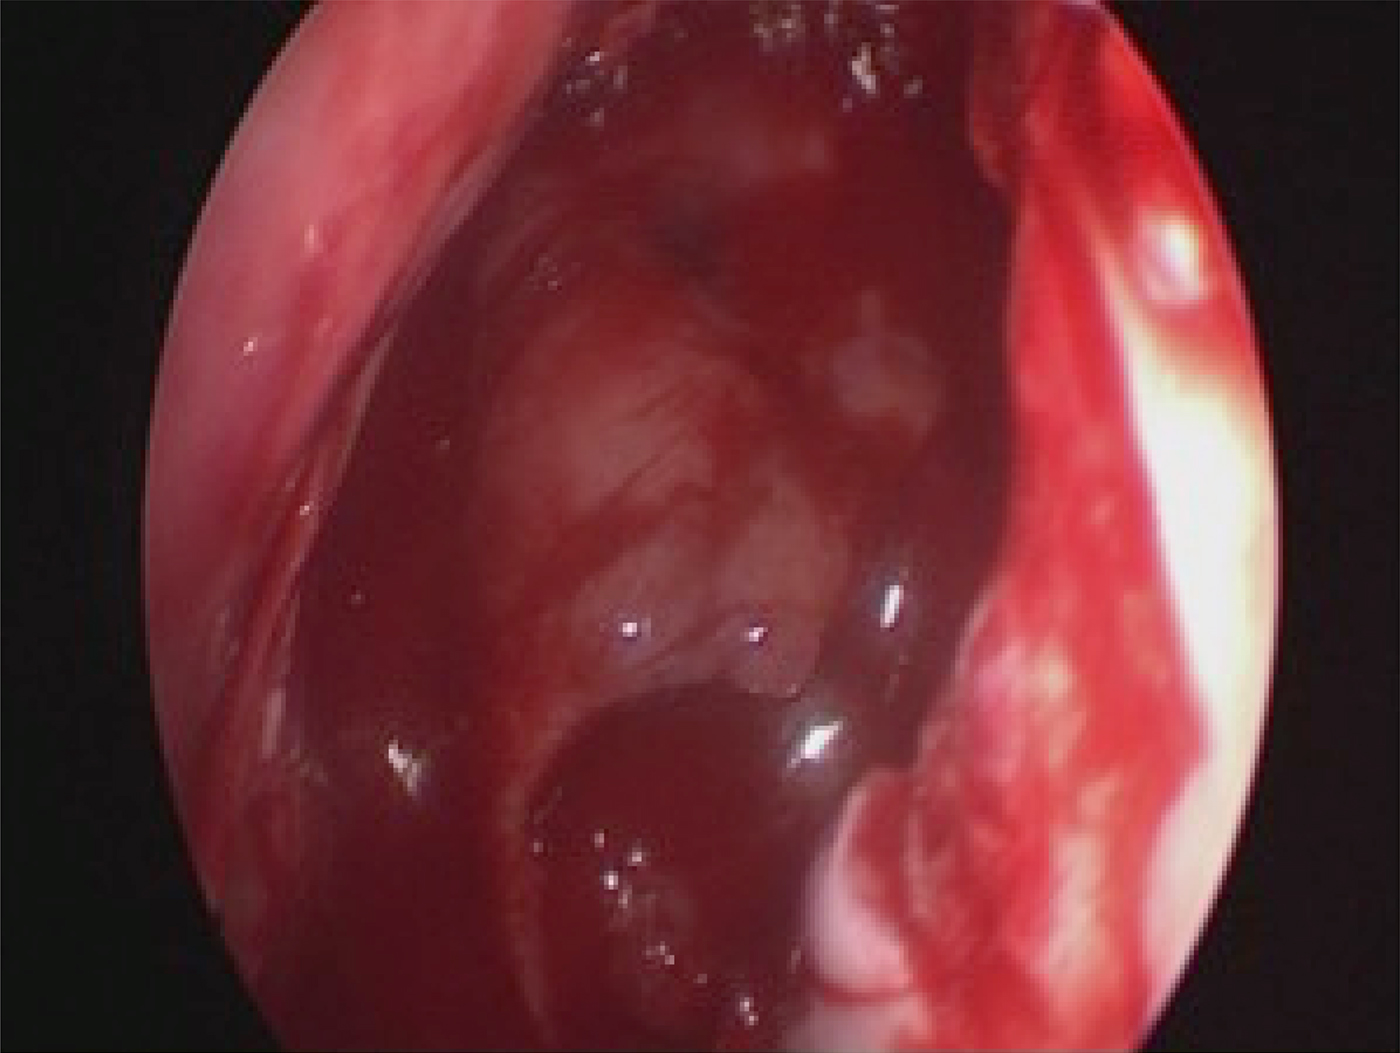

After the Draf procedure and removal of the tumour, the flap was used to cover the posterior wall of the sinus and the common recess (Figure 4). The flap was packed with gel foam and supported by a 12-French Foley catheter balloon. Nasal silicon buffers were inserted on both sides of the septum.

Fig. 4 Endoscopic image of the patient during surgery.

No major complication was reported during or after the operation. At the 24-month follow up, no recurrence of the osteoma was evident and the common recess was no smaller than 50 per cent of that at the end of surgery (Figures 5 and 6).

Fig. 5 Endoscopic image of the patient 24-months post-operatively.